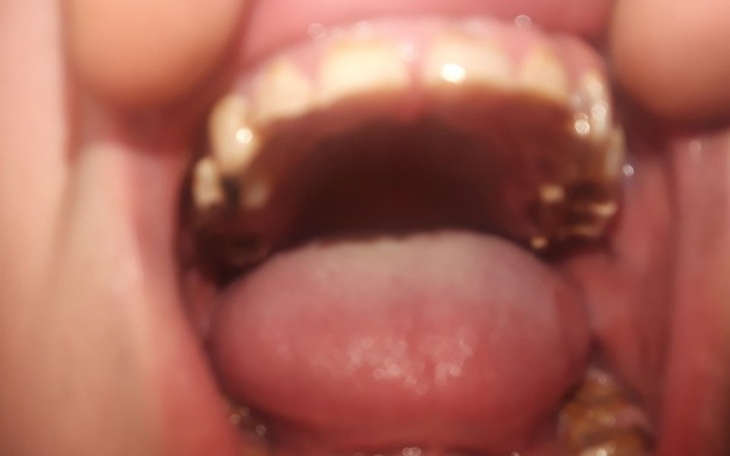

Jednak chemia wyruszyła mi zdrowie a także uzębienie.

Nie jestem w stanie normalnie jeść,

Każdy kęs sprawia ból .

▪Naprawa zębów które da się jeszcze odratować to kwota 150 zł za jednego zęba a jest ich ponad 15 więc wynosi to 1500zł +

▪Proteza na górną części szczęki a także nadlanie zębów to koszt 3500+

▪Leczenie kanałowe zębów dla których jest to ostatni ratunek 400 zł za jednego zęba a takich zębów jest 5.